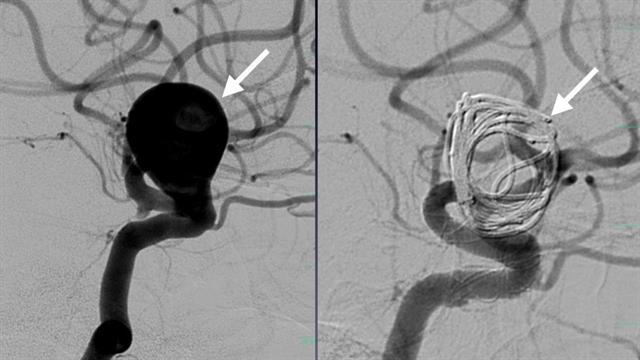

Το ανεύρυσμα της ασθενούς αντιμετωπίστηκε άμεσα με επιτυχή εμβολισμό από την Ομάδα Εμβολισμών του νοσοκομείου. Αυτή η ελάχιστα επεμβατική πράξη περιλαμβάνει την πλοήγηση καθετήρων μέσω του αγγειακού συστήματος στο σημείο του ανευρύσματος και την τοποθέτηση σπειραμάτων ή στεντ, για την αποτροπή της ροής του αίματος στο ανεύρυσμα, αποκλείοντάς το αποτελεσματικά.

Η επέμβαση αυτή όχι μόνο της έσωσε τη ζωή, αλλά βοήθησε στη γρήγορη ανάρρωσή της. Μέρα με τη μέρα, βελτιώθηκε σημαντικά ο πονοκέφαλος και τώρα είναι έτοιμη να πάρει εξιτήριο. Μέχρι σήμερα, στο κέντρο έχουν λάβει θεραπεία πάνω από 35 ασθενείς με σοβαρά και απειλητικά για τη ζωή προβλήματα.

Τα εγκεφαλικά ανευρύσματα και οι αρτηριοφλεβικές δυσπλασίες αποτελούν από τις πιο σοβαρές και περίπλοκες νευρολογικές καταστάσεις που μπορούν να προκαλέσουν απειλητική για τη ζωή εγκεφαλική αιμορραγία και απαιτούν ειδική θεραπεία. Το νέο Κέντρο προσφέρει ενδοαγγειακές θεραπείες, μία μέθοδο λιγότερο επεμβατική από την παραδοσιακή χειρουργική επέμβαση η οποία συχνά μπορεί να οδηγήσει σε ταχεία ανάρρωση.

«Περιλαμβάνει μια μικρή τομή, συνήθως στη βουβωνική χώρα, και τη χρήση μικρών καθετήρων που φτάνουν στον εγκέφαλο μέσω των αγγείων του σώματος. Εδώ, οι ιατροί μπορούν να αντιμετωπίσουν την πάθηση με διάφορους τρόπους, όπως με σπειράματα, τοποθέτηση στεντ ή χρησιμοποιώντας ειδική ιατρική «κόλλα», εξηγεί η κα Πολίτη.